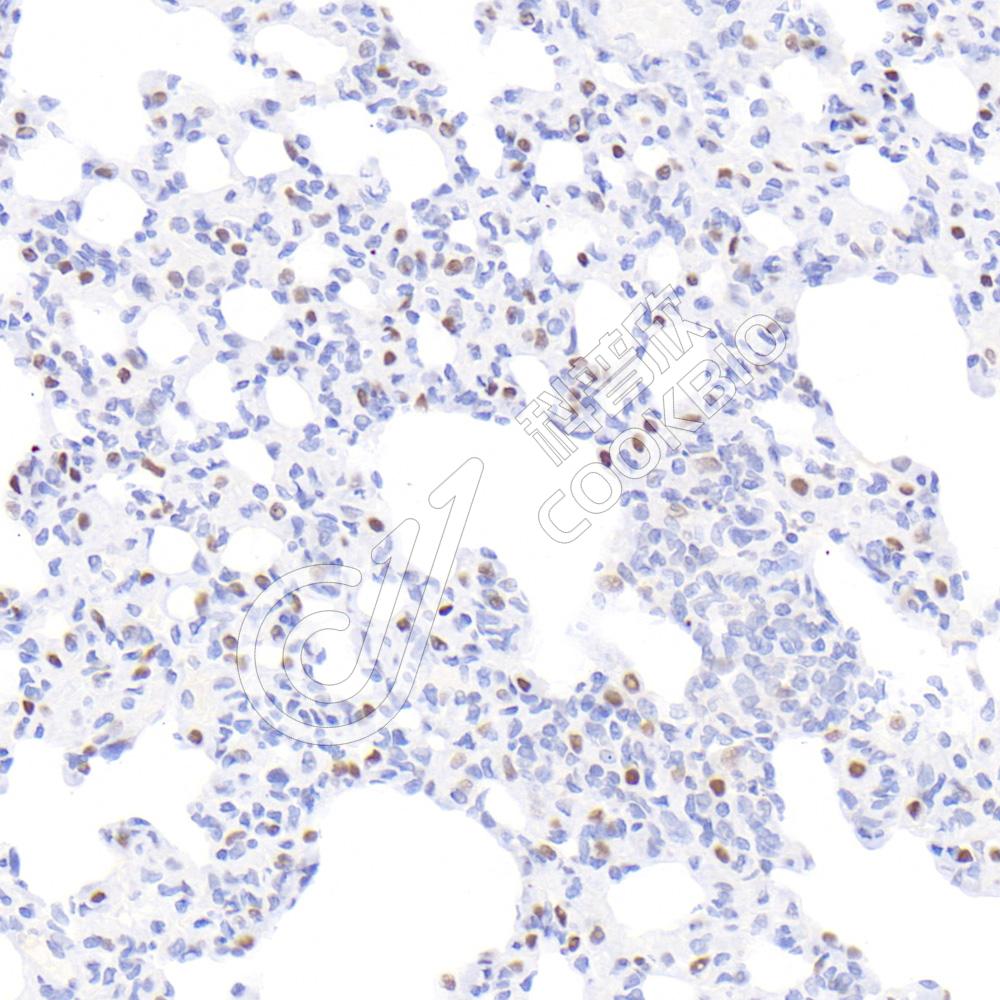

IHC检测TTF1(Thyroid transcription factor 1)蛋白(货号 K2366504).

样品: 大鼠肺, 4%多聚甲醛 (货号KSG1101) 固定12-24小时.

抗原修复: 柠檬酸抗原修复液(干粉, pH 6.0) (KSG1201), 高压锅均匀喷气计时2分钟.

—抗: 1: 800稀释, 4℃ 孵育过夜.

二抗: S-vision免疫组化多聚二抗(山羊抗小鼠), 即用型(货号KB3903), 室温孵育20分钟.